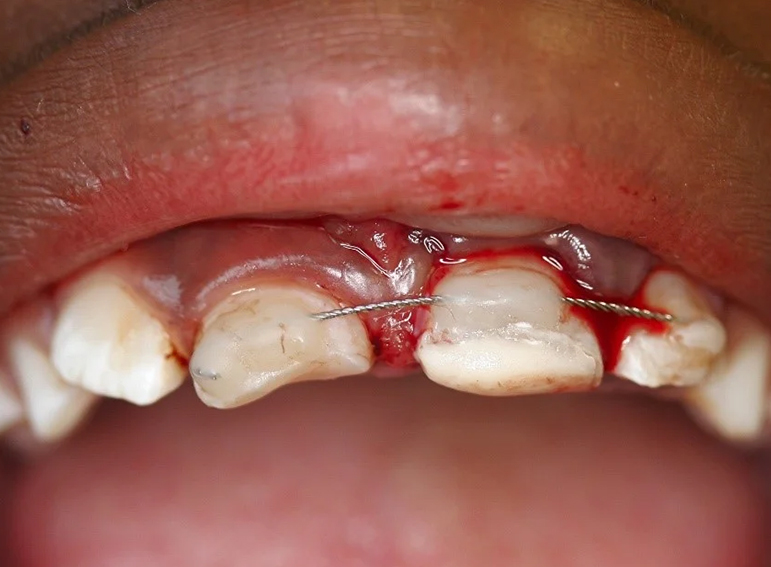

Surgical extrusion, root canal and apexification treatment of UL1 and composite build ups of UR1 and UL1 following dental trauma.